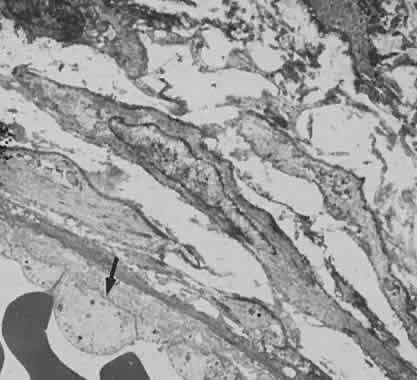

Much attention has been given to the histopathologic nature of the “snowbanks,” which has been studied by both light and electron microscopy.52,54,56–58 These fibrovascular-glial proliferations are found over the inferior pars plana and peripheral retina. They are composed of dense connective tissue derived from condensed, collapsed vitreous and often are vascularized. These vessels may reveal features of high endothelial venules (Fig. 8). Such endothelia are known to play a role in the homing of activated lymphocytes.54 The cellular elements of these membranes include fibroglial cells that are believed, based on their electron microscopic characteristics, to represent fibrous astrocytes, as well as nonpigmented ciliary epithelial cells, fibroblasts, and lymphocytes (Fig. 9).52–55,59,60 The vitreous is infiltrated by chronic inflammatory cells, and despite the nongranulomatous nature of the inflammatory component in the snowbanks, vitreous snowballs have been reported to consist of epithelioid cell granulomas.52

Fig. 8. Electron micrograph from eye with pars planitis (see also Fig. 9) showing collagen deposition and high endothelial venules (arrow).